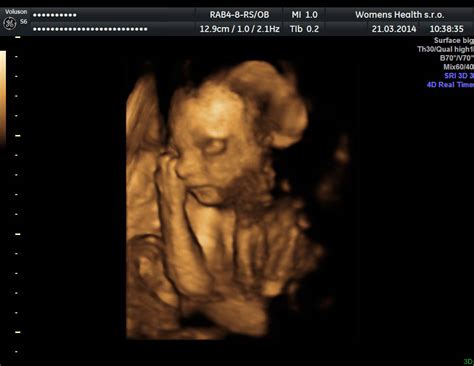

- 3D ultrazvuk: Táto technológia vytvára trojrozmerný statický obraz bábätka. Umožňuje detailnejšie zobrazenie tváričky, končatín, mimiky a pohybov rúk v oveľa realistickejšej podobe ako 2D snímky. Rodičia si túto možnosť často vyberajú pre emocionálny zážitok a možnosť získať fotografickú pamiatku.

- 4D ultrazvuk: Predstavuje "živú verziu" 3D ultrazvuku, pretože zachytáva pohyby bábätka v reálnom čase. Môžete vidieť, ako si dieťatko cmúľa palec, zíva, usmieva sa alebo sa hýbe, to všetko v trojrozmernom zobrazení a v reálnom čase. Štvrtý rozmer "D" tu predstavuje práve čas, teda dynamiku pohybu.

Na 4D ultrazvuku môžete vidieť detaily tváričky ako nosík, pery, viečka, a dokonca aj mimiku - bábätko môže otvárať a zatvárať oči, zívať, usmievať sa alebo si cmúľať palec. Všetko toto sa zobrazuje v reálnom čase, ako na videu. Okrem vizuálneho zážitku ultrazvuk zachytáva aj dôležité pohyby rúk a nožičiek, ktoré sú znakom dobrého vývoja. Lekár môže skontrolovať aj umiestnenie placenty, množstvo plodovej vody a základné proporcie bábätka.